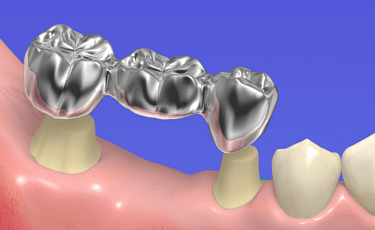

歯を失ったときの治療法には“ブリッジ、入れ歯、インプラント”があげられます。

ブリッジ ![]() |

失った歯の部分の左右の歯を削り、